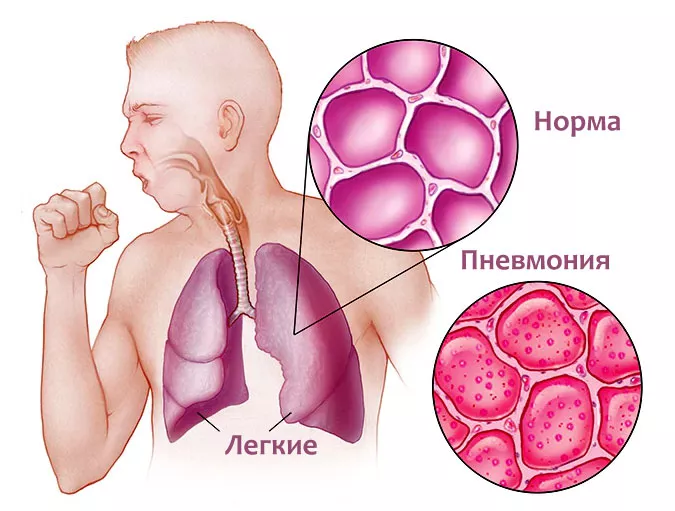

Фотографии бактерий, вызывающих бактериальные пневмонии у животных

Раздел: Другие животные